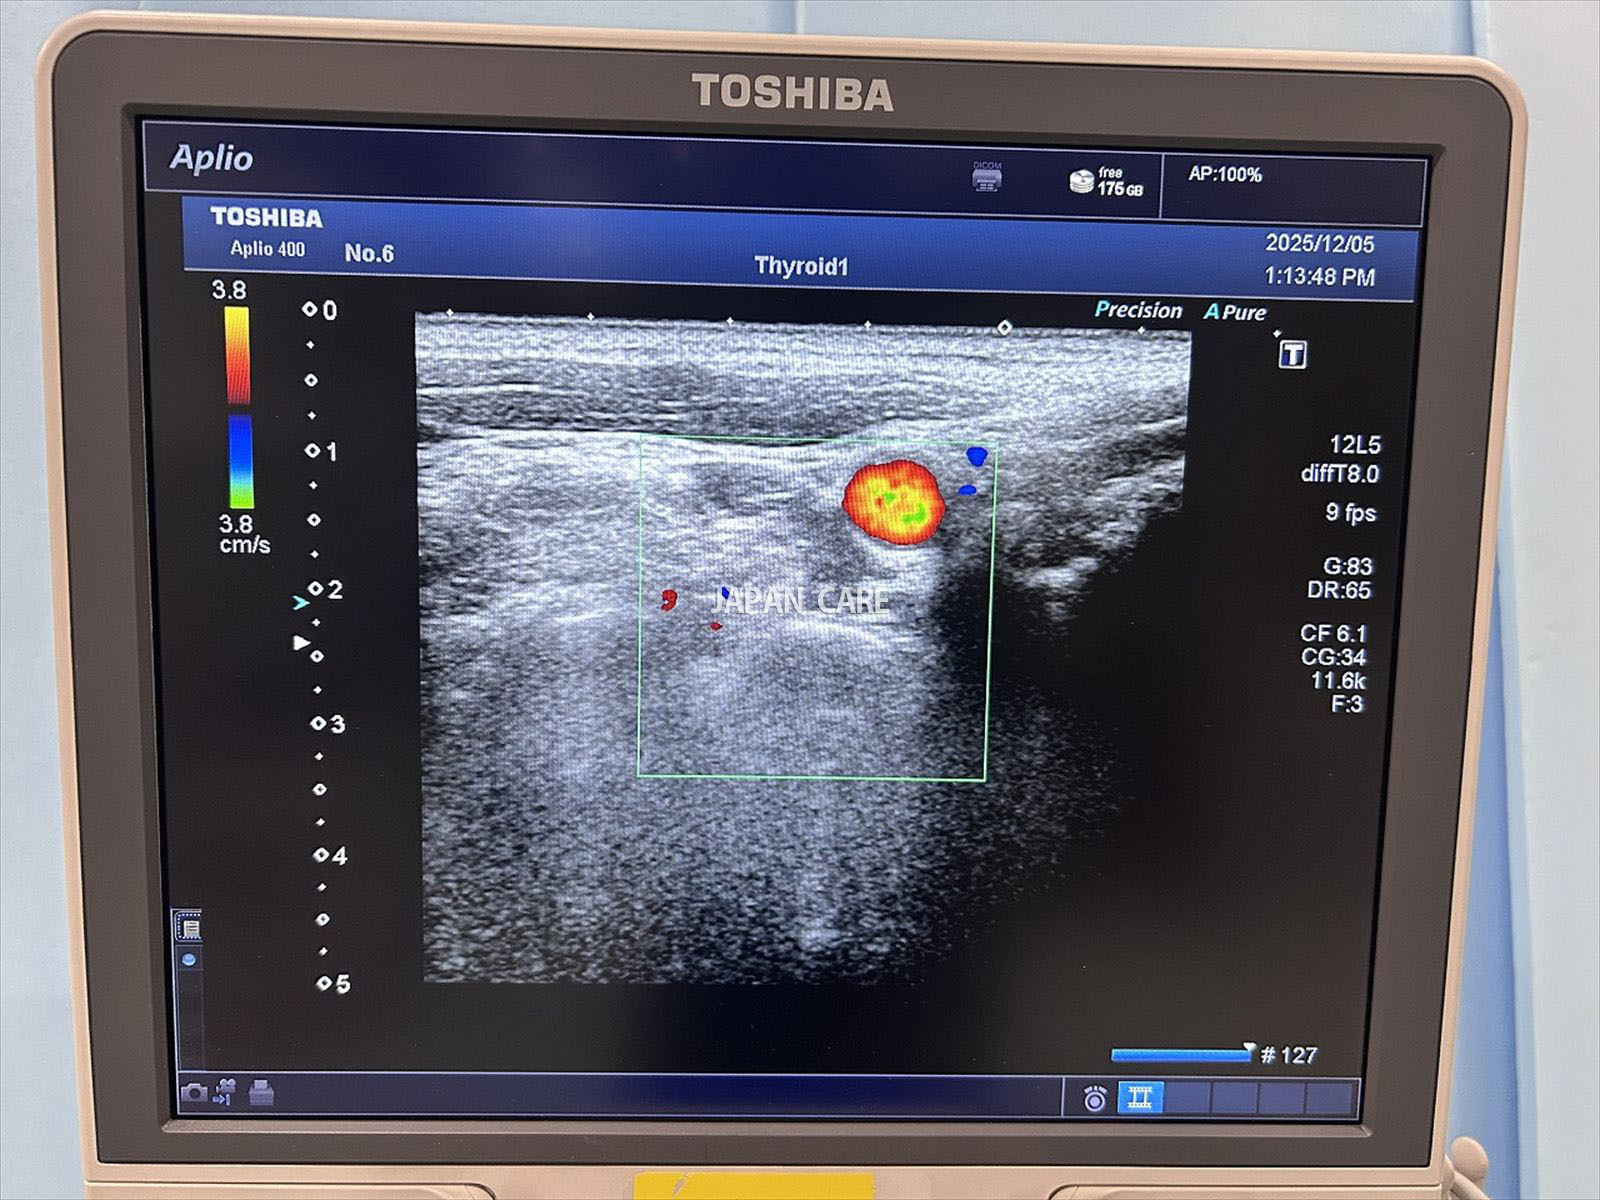

Toshiba Ultrasound APLIO 400

Model

APLIO 400

Manufacturer

Toshiba

Year

2014

2 probes :

PLT-805AT

PVT-375BT